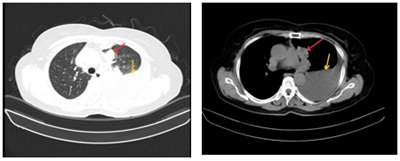

Case lâm sàng: Ứng dụng trí tuệ nhân tạo (Artificial intelligence – AI) trong chẩn đoán và điều trị sớm Ung thư phổi tại Trung tâm Y học hạt nhân và Ung bướu, Bệnh viện Bạch Mai

Theo GLOBOCAN 2022, ung thư phổi đứng đầu về số ca mới mắc (2.480.301 ca mới mắc chiểm 12.4%) và dẫn đầu số ca tử vong (1.817.172 ca tử vong chiếm 18.7%) trên toàn thế giới.  Tại Việt Nam tỷ lệ mắc ung thư phổi xếp thứ ba 13,5% lệ tử vong...